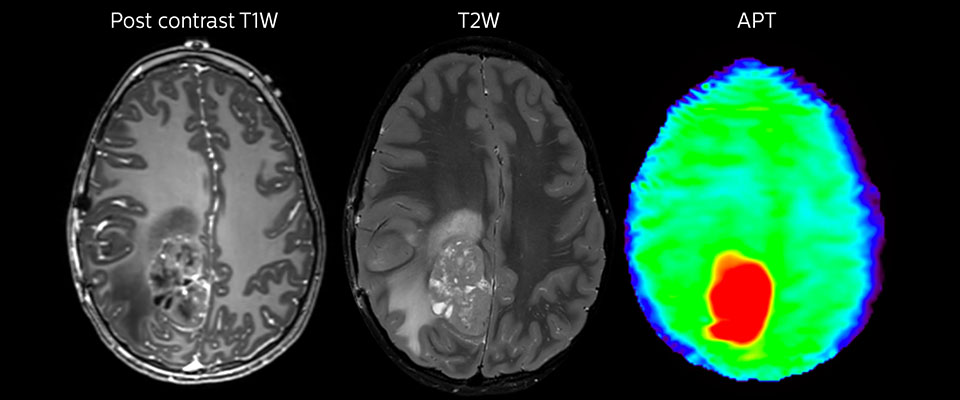

Large metastatic brain lesion

This 10-year-old patient underwent Ewing’s sarcoma tumor resection 7 years ago, but was found to now have a large metastatic lesion in the brain. This lesion shows clearly increased APT signal.